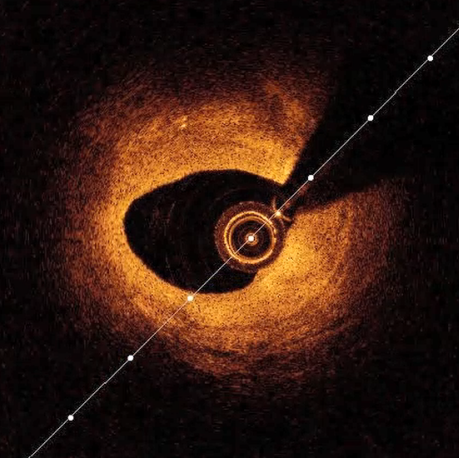

因此,术者使用3.0*15mm高压球囊14-20atm及3.75*13mm高压球囊12-20atm进行后扩张,再次使用微创阿格斯™OCT评价即刻手术效果,可见生物可吸收支架膨胀及贴壁良好,夹层被生物可吸收支架覆盖,复查造影提示管腔残余狭窄<10%,血流TIMI 3级,未见夹层及穿孔,手术取得圆满成功。

OCT下可见管腔狭窄程度明显减轻,生物可吸收支架小梁贴附在管壁上